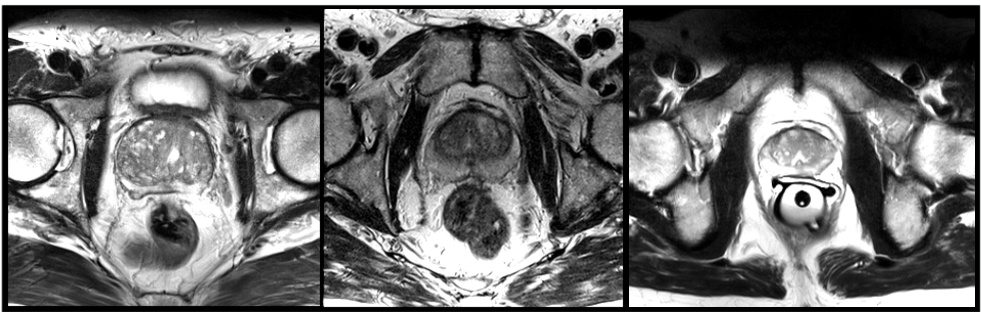

Fig. 1. Slices from MRI volumes depicting prostate. This data is part of the PROMISE 2012 challenge dataset [7].

Our CNN is trained end-to-end on a dataset of prostate scans in MRI. An example of the typical content of such volumes is shown in Figure 1. All the volumes processed by the network have fixed size of $128\times128\times64$ voxels and a spatial resolution of $1\times1\times1.5$ millimeters.

我们的CNN在MRI前列腺扫描数据集上进行了端到端训练。图1展示了此类体积数据的典型内容示例。网络处理的所有体积数据都具有固定的$128\times128\times64$体素尺寸和$1\times1\times1.5$毫米的空间分辨率。